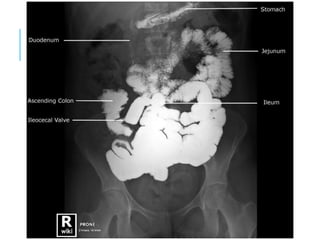

BARIUM STUDIES

Follow

Through